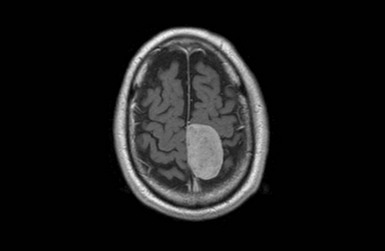

• Oncology (e.g. glioma, meningioma and metastases)

Postoperative seizures, reduced conscious level or altered neurology may herald intracranial complications such as oedema or bleeding. Repeat CT is needed after stabilising blood pressure and oxygenation. Sedating analgesics should generally be avoided. Paracetamol and codeine phosphate or small doses of morphine may be appropriate. NSAIDs impair platelet function and should be avoided early on in high-risk patients.